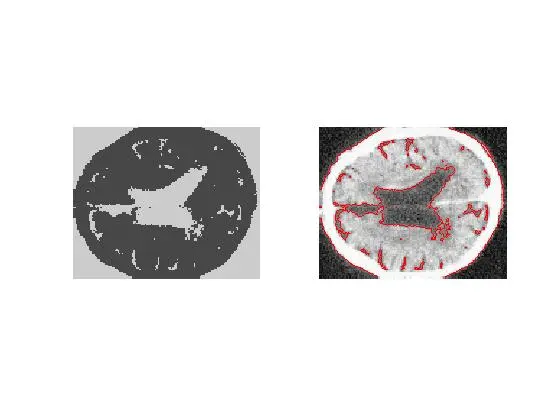

%%每运行两百次显示曲线和分片常数曲线

if mod(n,200)==0

nn=nn+1;

f=Img;

f(u>0)=c1;

f(u<0)=c2;

figure(nn+2);

subplot(1,2,1);imshow(uint8(f));

subplot(1,2,2);imshow(uint8(Img));

hold on;

[c,h]=contour(u,[0,0],'r');

hold off;

end

就可实现对人的大脑切片的分割, 见下图: